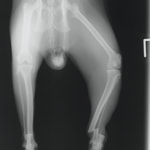

症例3:キルシュナーワイヤーのピンニングによる整復

ペルシャ猫 11ヶ月齢 雄

他院にて左大腿骨遠位の成長板骨折(salter-harrisⅠ型)が認められており、治療相談を目的として来院。当院にて、キルシュナーワイヤーを用いたピンニングにより骨折部位の整復を行いました。術後の経過は良好で、現在も経過観察中です。

術前レントゲン

術後レントゲン